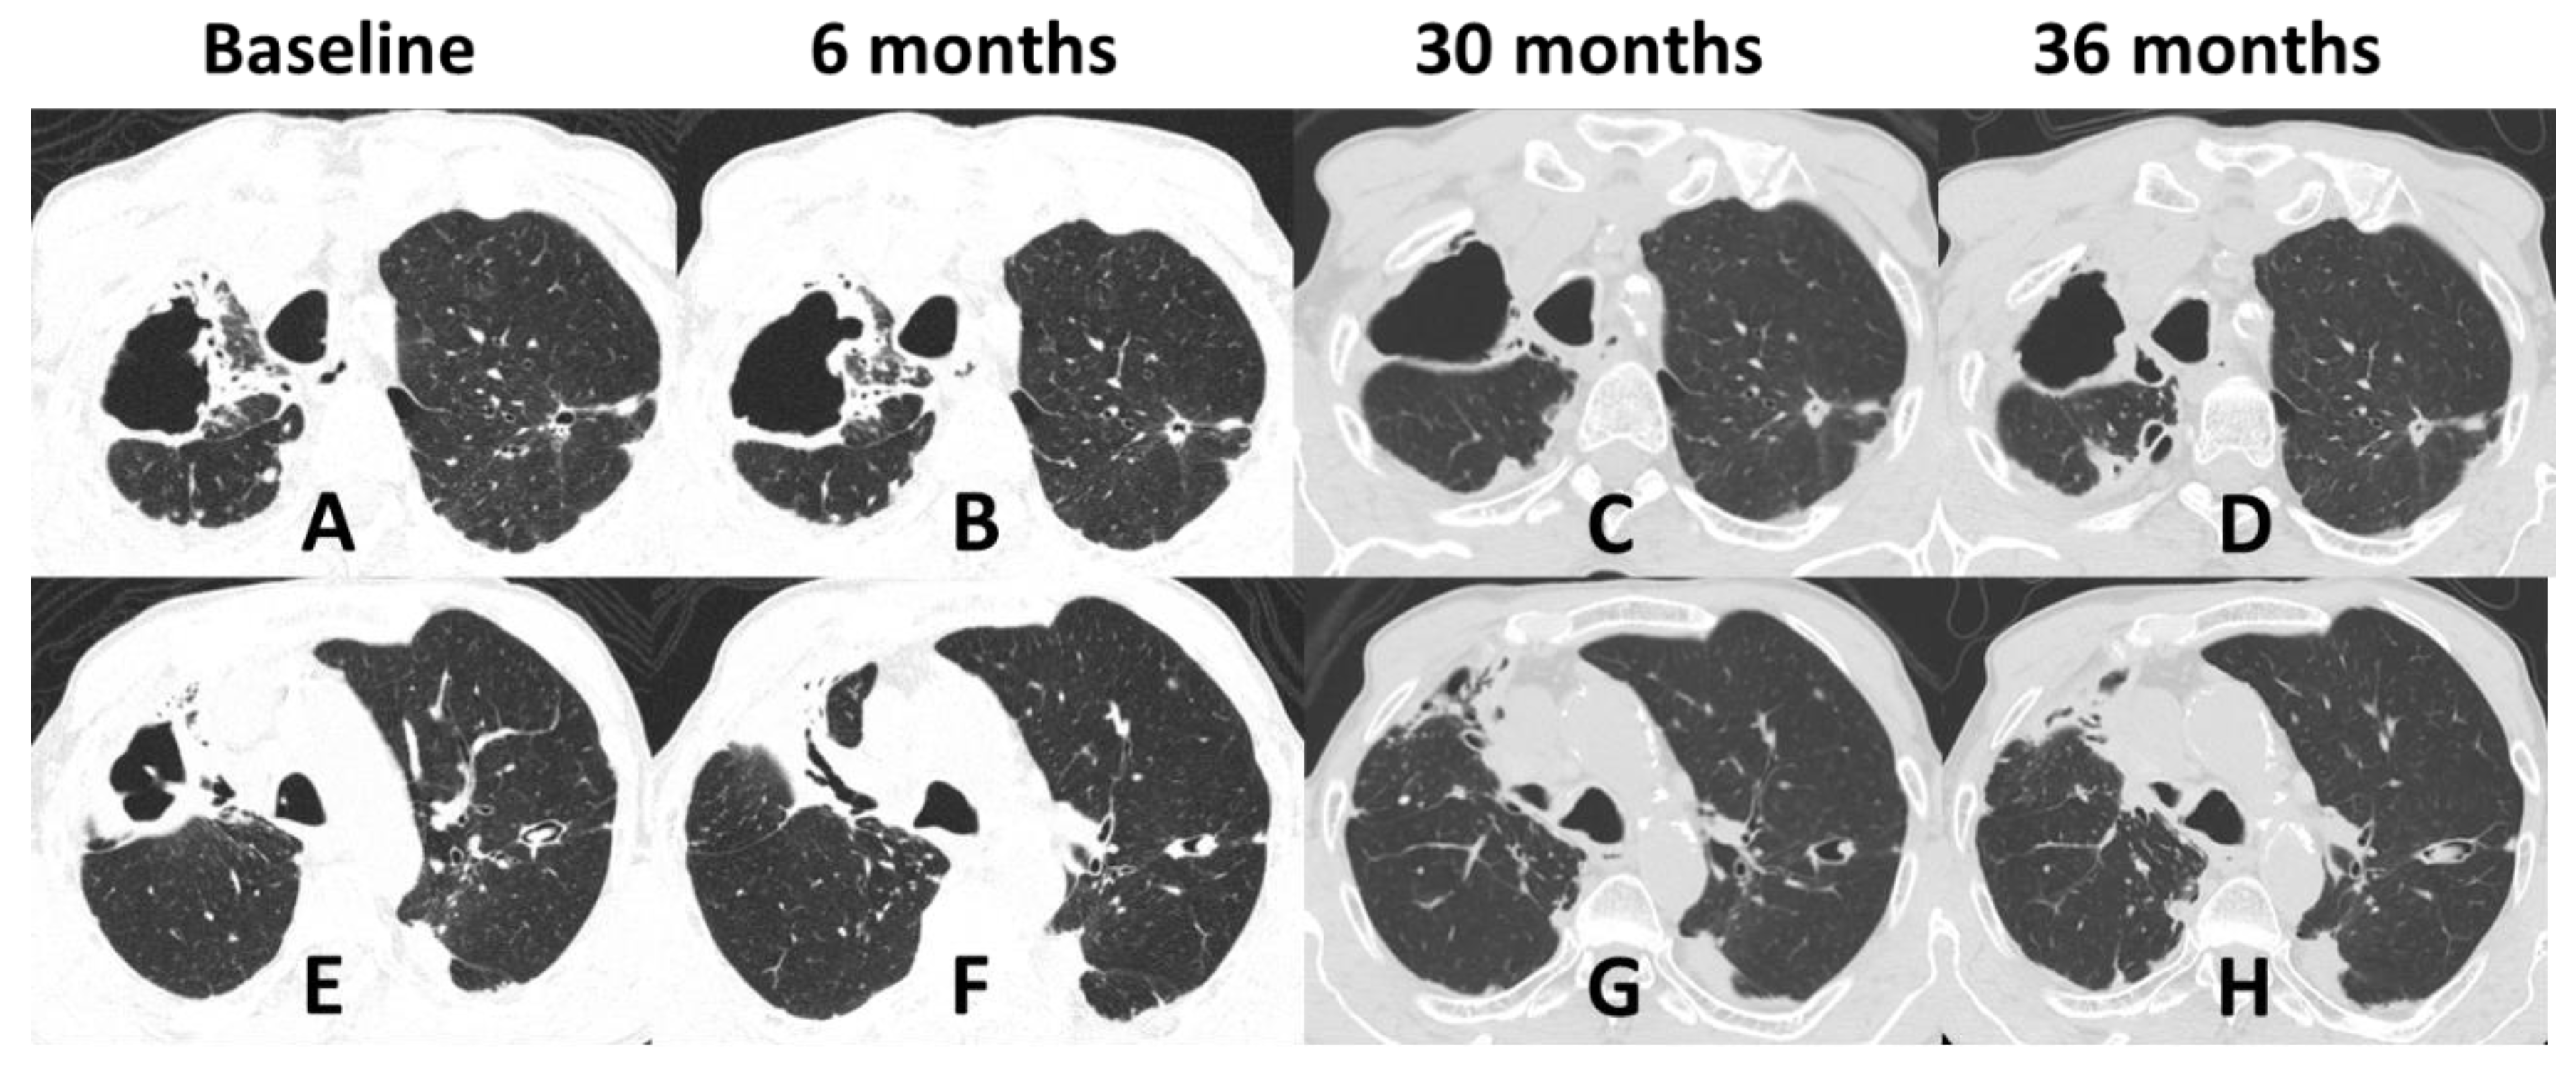

3.3. Radiological Patterns

| 1 (2018) | Male | 71 | None | Primary pulmonary | Lungs | Alcoholism COPD | No | Reticulonodular infiltrate; cavitation; fibrosis Unilateral/Multilobar | Sputum; BAL | ITZ; PSZ | Under treatment |

| 2 (2018) | Male | 63 | Contact with cat | Disseminated | Lungs, bone | Alcoholism COPD | No | Cavitation; fibrosis; hilar lymphadenopathy Unilateral/Unilobar | Sputum; BAL | ITZ; AmB; PSZ | Under treatment |

| 14 (2018) | Female | 20 | Contact with diseased cats | Disseminated | Skin, lungs, bones, upper airways | HIV (CD4 = 56 cells/mm3) Alcoholism | Pneumocystis pneumonia | Cavitation; reticulonodular infiltrate; consolidation | Sputum | ITZ; AmB; PSZ | Cure |